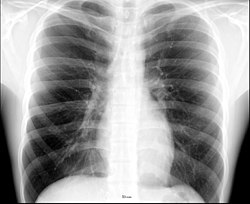

Placa posteroanterior de tórax en el sujeto normal. -